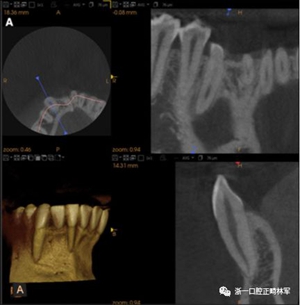

臨床檢查顯示固定保持器完好,弓絲沒有斷裂(圖13)。在下頜右側(cè)中切牙唇側(cè)和鄰近側(cè)切牙的舌側(cè)注意到有牙齦退縮。這些牙齒在退縮方向上存在顯著的扭矩差異。下頜的左側(cè)尖牙頰側(cè)錯(cuò)位,而右側(cè)尖牙舌側(cè)傾斜。三維射線照片證實(shí)了下頜右側(cè)尖牙面?zhèn)妊啦酃菃适?,右?cè)中切牙的喪失程度較輕。右側(cè)側(cè)切牙根也從舌側(cè)骨面上扭轉(zhuǎn)出來(圖14)。

圖14.三維立體圖像:A,面部和B,切牙根部的舌側(cè),剛?cè)〕龉潭ㄉ鄠?cè)保持器后。